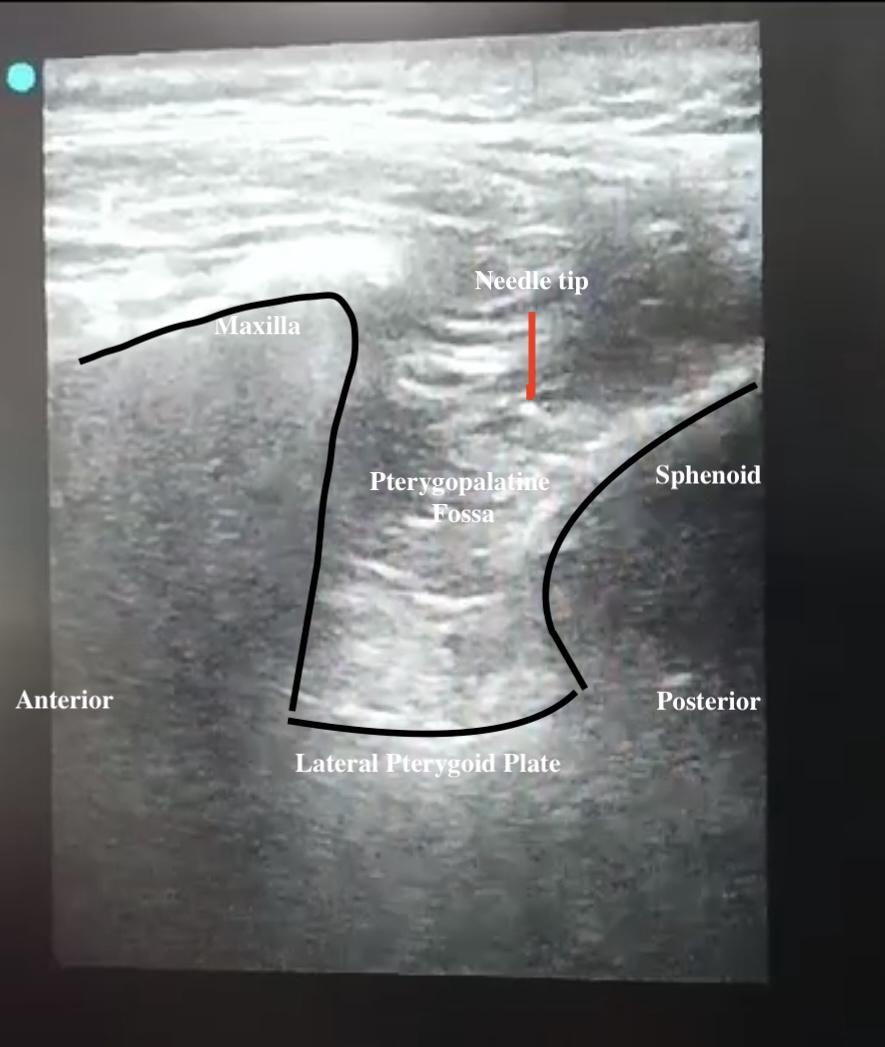

Fig. 1: Sonoanatomy of supra-zygomatic approach sphenopalatine ganglion block

The SPGB was administered under sterile conditions using an ultrasound-guided transcutaneous suprazygomatic approach on the affected side. A total of 4 ml of 0.5% bupivacaine was injected. The procedure was performed with the patient in the supine position, employing a linear ultrasound probe (5–12 MHz). The transducer was positioned in the infrazygomatic region on the tumour side, over the maxilla, and angled 45° cephalad. In this angle, PPF was visualized anteriorly between the maxilla and posteriorly between the pterygoid process [fig. 1]. A 25-gauge spinal needle was inserted above the zygomatic arch and lateral to the posterior orbital rim. It was then advanced 45° caudally and 10° anteriorly, directed toward the PPF. Afterward, 4 ml of 0.5% bupivacaine was injected over 15-20 sec, while the spread of the local anaesthetic was observed under USG. Time required to perform the technique is defined as the time from the beginning of scanning until the study drug injection and will be recorded. Intraoperative analgesia was supplemented with bolus doses of fentanyl (1μg/kg) if mean arterial pressure (MAP) and/or heart rate (HR) increased by more than 20% from baseline. Target intraoperative MAP of 60–65 mmHg was maintained by the adjustment of the nitroglycerine infusion from 0.5 to 10ug/kg/min according to the patient’s response. The total intraoperative fentanyl requirements were recorded. Hemodynamic parameters, including HR, MAP, and SpO₂, were recorded every 30 min. Bradycardia (HR<45 beats/min) was managed with intravenous atropine (300 μg).